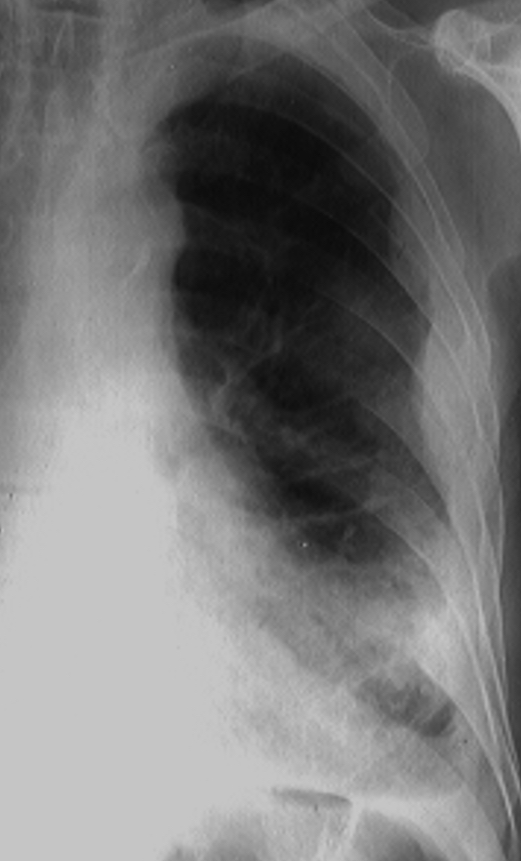

Rx toracică, incidență P-A (centrată pe hemitoracele drept)

DESCRIERE:

în 1/3 sup. a hemitoracelui drept → opacitate de formă triunghiulară, intensitate medie-mare, omogenă

caracter retractil → tracționează traheea și mediastinul de partea afectată + retracția scizurii orizontale (aspect concav)

adenopatii hilare

pahipleurită diafragmatică → îngroșarea pleurei + tracțiuni fibroase

DX: atelectazie prin NBP central endobronșic (pe bronhia lobară sup. dr.)

DD: pneumonie lobară - nu are caracter retractil, prezintă bronhogramă aerică